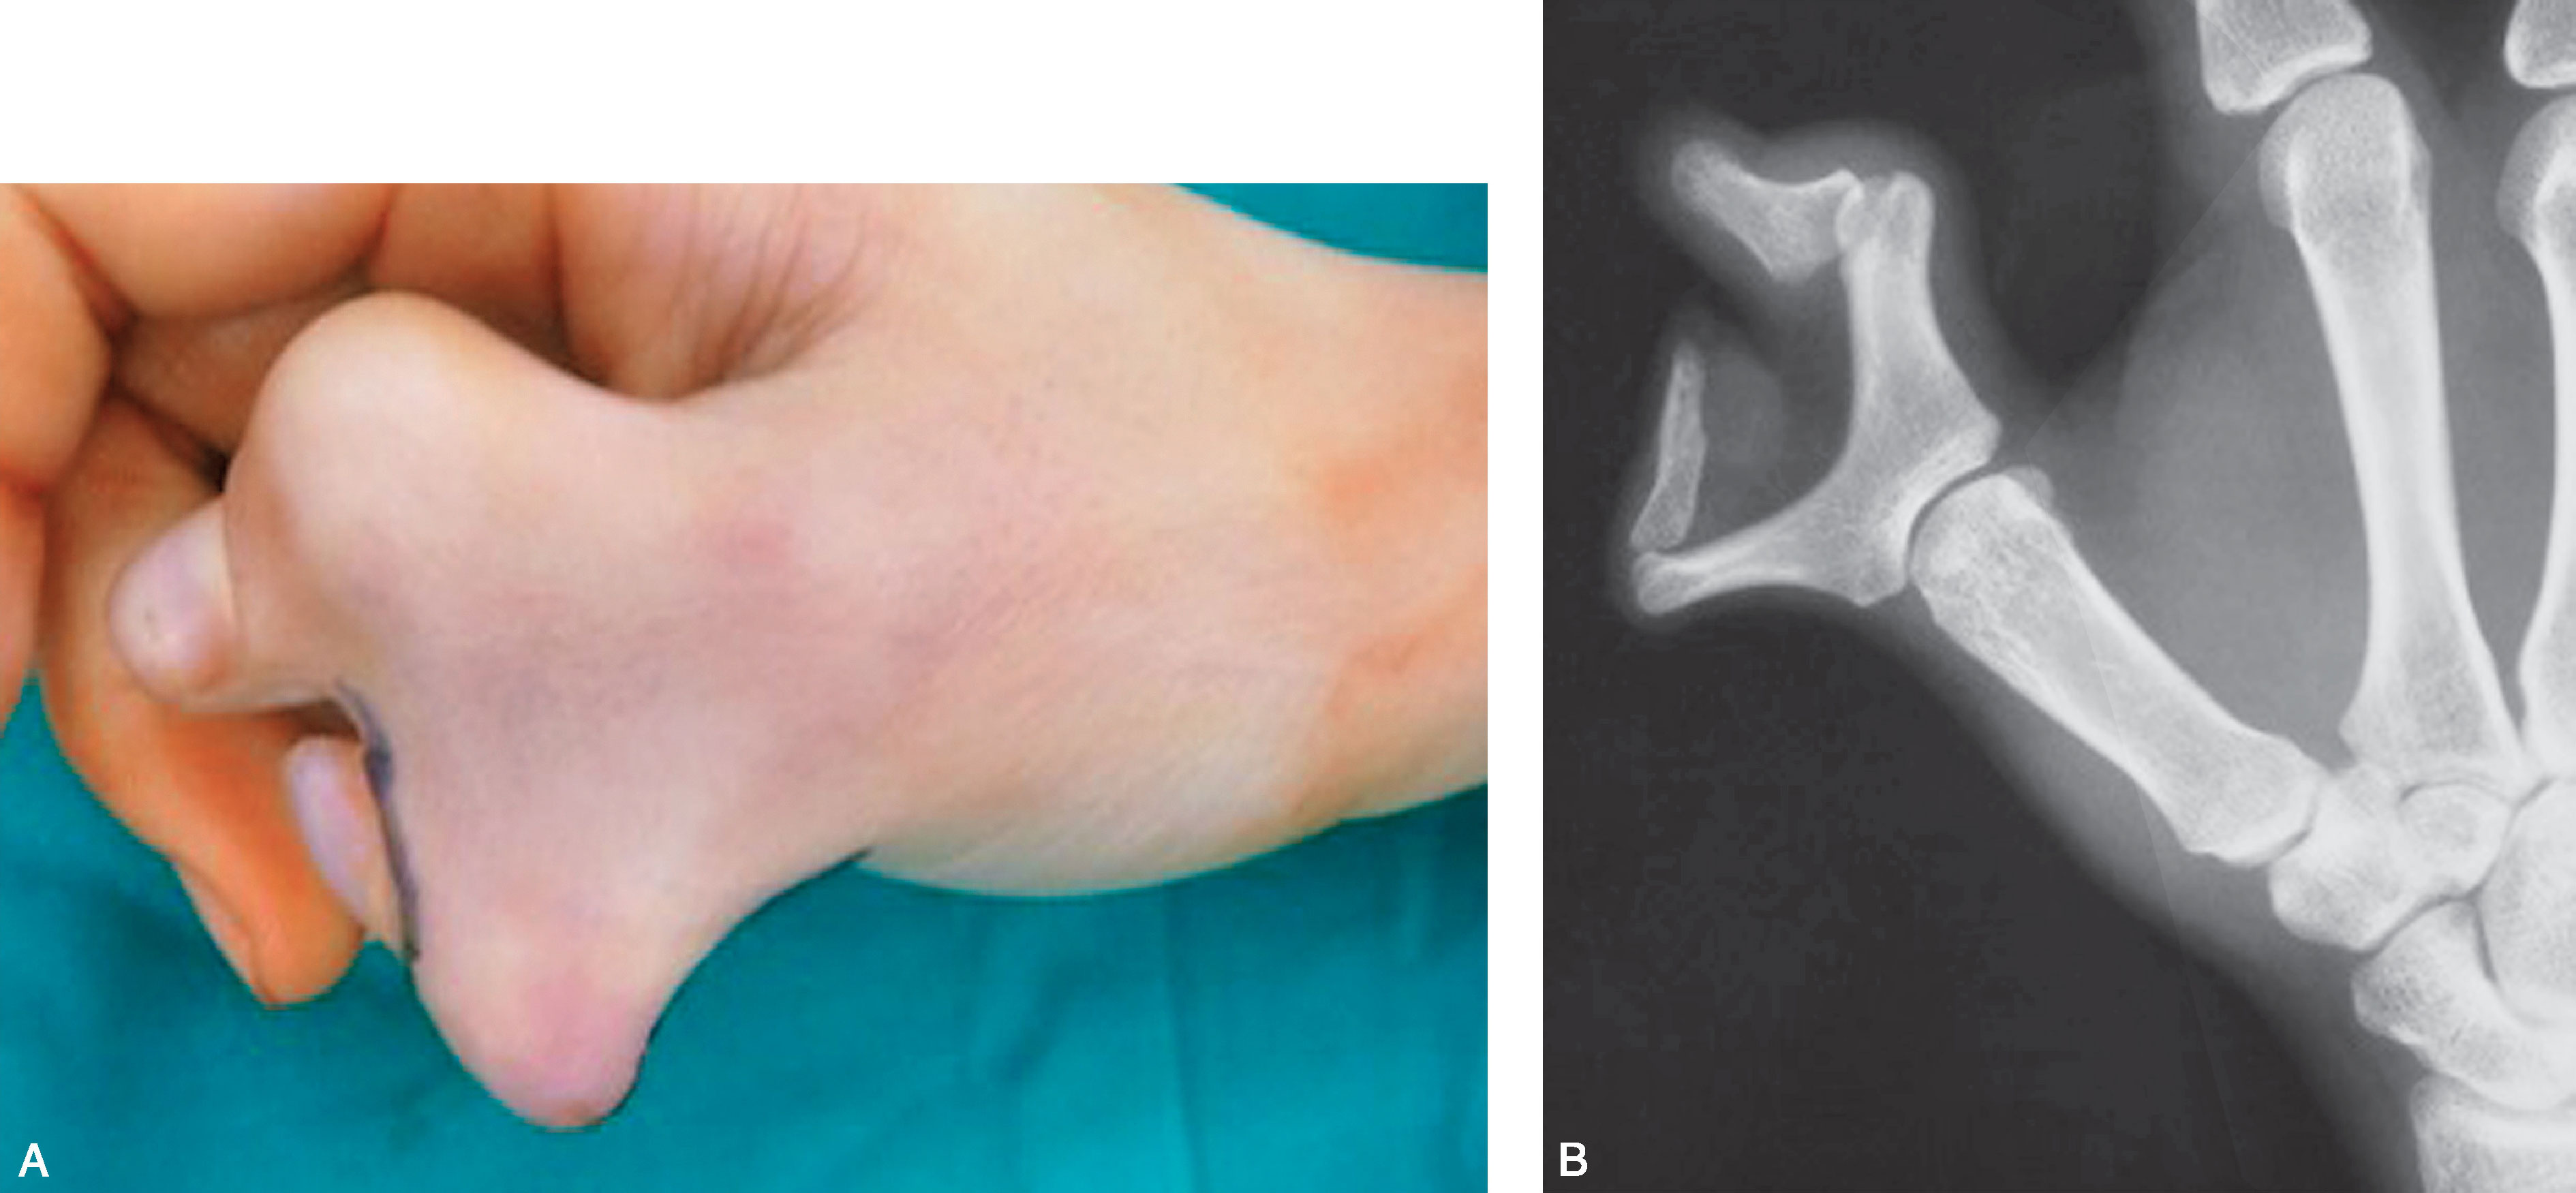

1.Ⅰ型 末节指骨未完全分裂,近节指骨正常或不正常,共用一个骨骺,并与近节指骨远端形成关节(图2-1-1~图2-1-4)。

图2-1-1 Ⅰ型病例1

A.主拇指与次拇指外形差异较大,各自有独立的指甲,远节尺偏(左侧);B.X 线片显示,虽然指骨远端分开,但基底共用一个骨骺,重建时需手术切除部分桡侧骨骺板,远节指骨尺偏需行近节指骨远端桡侧闭合楔形截骨,以纠正远节手指的尺偏畸形